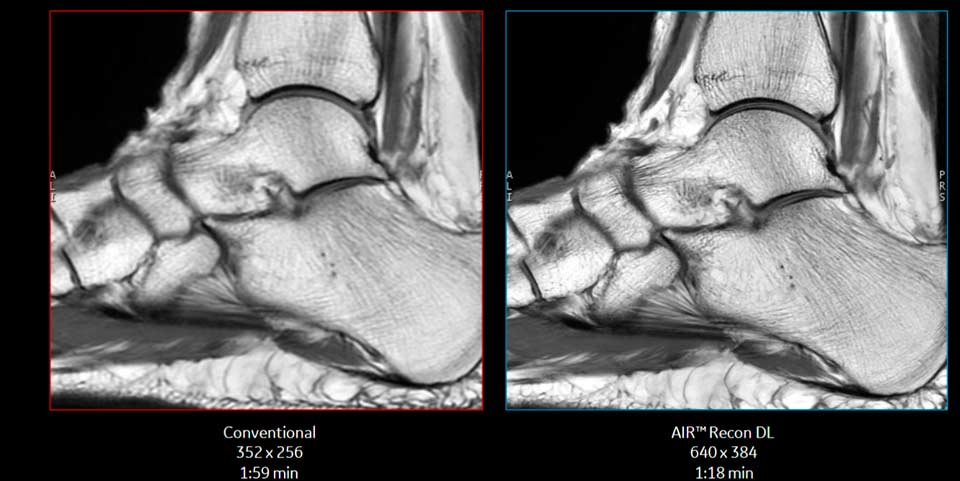

En resonancias magnéticas, Dinamarca pone como ejemplo la pionera aplicación AIR Recon DL de GE Healthcare, que utiliza un algoritmo de aprendizaje profundo para mejorar la reconstrucción de imágenes y, en esencia, «elimina el ruido» de los datos digitales sin procesar, lo que potencia los diagnósticos con estructuras anatómicas mucho más nítidas y finas de lo que se conocía hasta ahora. “Existe hoy una necesidad imperiosa de que el diagnóstico sea eficiente, mejorando la productividad y reduciendo el tiempo de examen. Nuestro algoritmo de IA de AIR Recon DL permite así mejorar la experiencia del paciente y del cuerpo clínico, con mejoras manifiestas en la calidad de imagen”, dice Dinamarca.